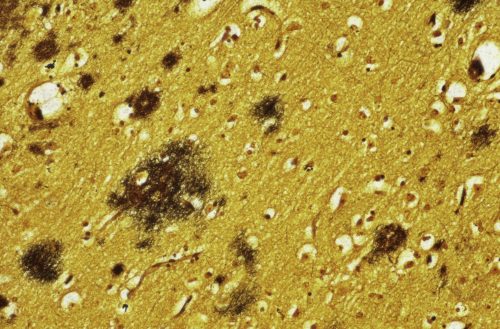

1906 beskrev den tyska läkaren Alois Alzheimer för första gången sjukdomen som fått hans namn. När han obducerade Auguste Deter, som avled i 50-årsåldern efter att ha haft minnesproblem och andra symtom på demens i flera år, såg han sjukliga förändringar i hjärnan. Mellan de döda nervcellerna observerade han mikroskopiskt små klumpar och inne i själva cellkroppen fanns något som liknande små trådiga nystan.

I dag vet vi att klumparna och nystanen är ansamlingar av två olika proteiner, beta-amyloid och tau. Båda finns i den friska hjärnan men vid sjukdomen går något fel. Beta-amyloid formar klumparna som kallas plack som lagras in mellan nervcellerna och det bildas trassliga nystan av tau inuti cellerna.

Ansamlingen av plack och trassliga proteinnystan gör att kontaktvägarna mellan nervcellerna blockeras och impulser får allt svårare att nå fram till olika delar av hjärnan. Efterhand sprider sig de sjukliga förändringarna och gör att en allt större del av hjärnans nervceller förtvinar och dör. Som en följd av det blir vissa delar av hjärnan mindre.